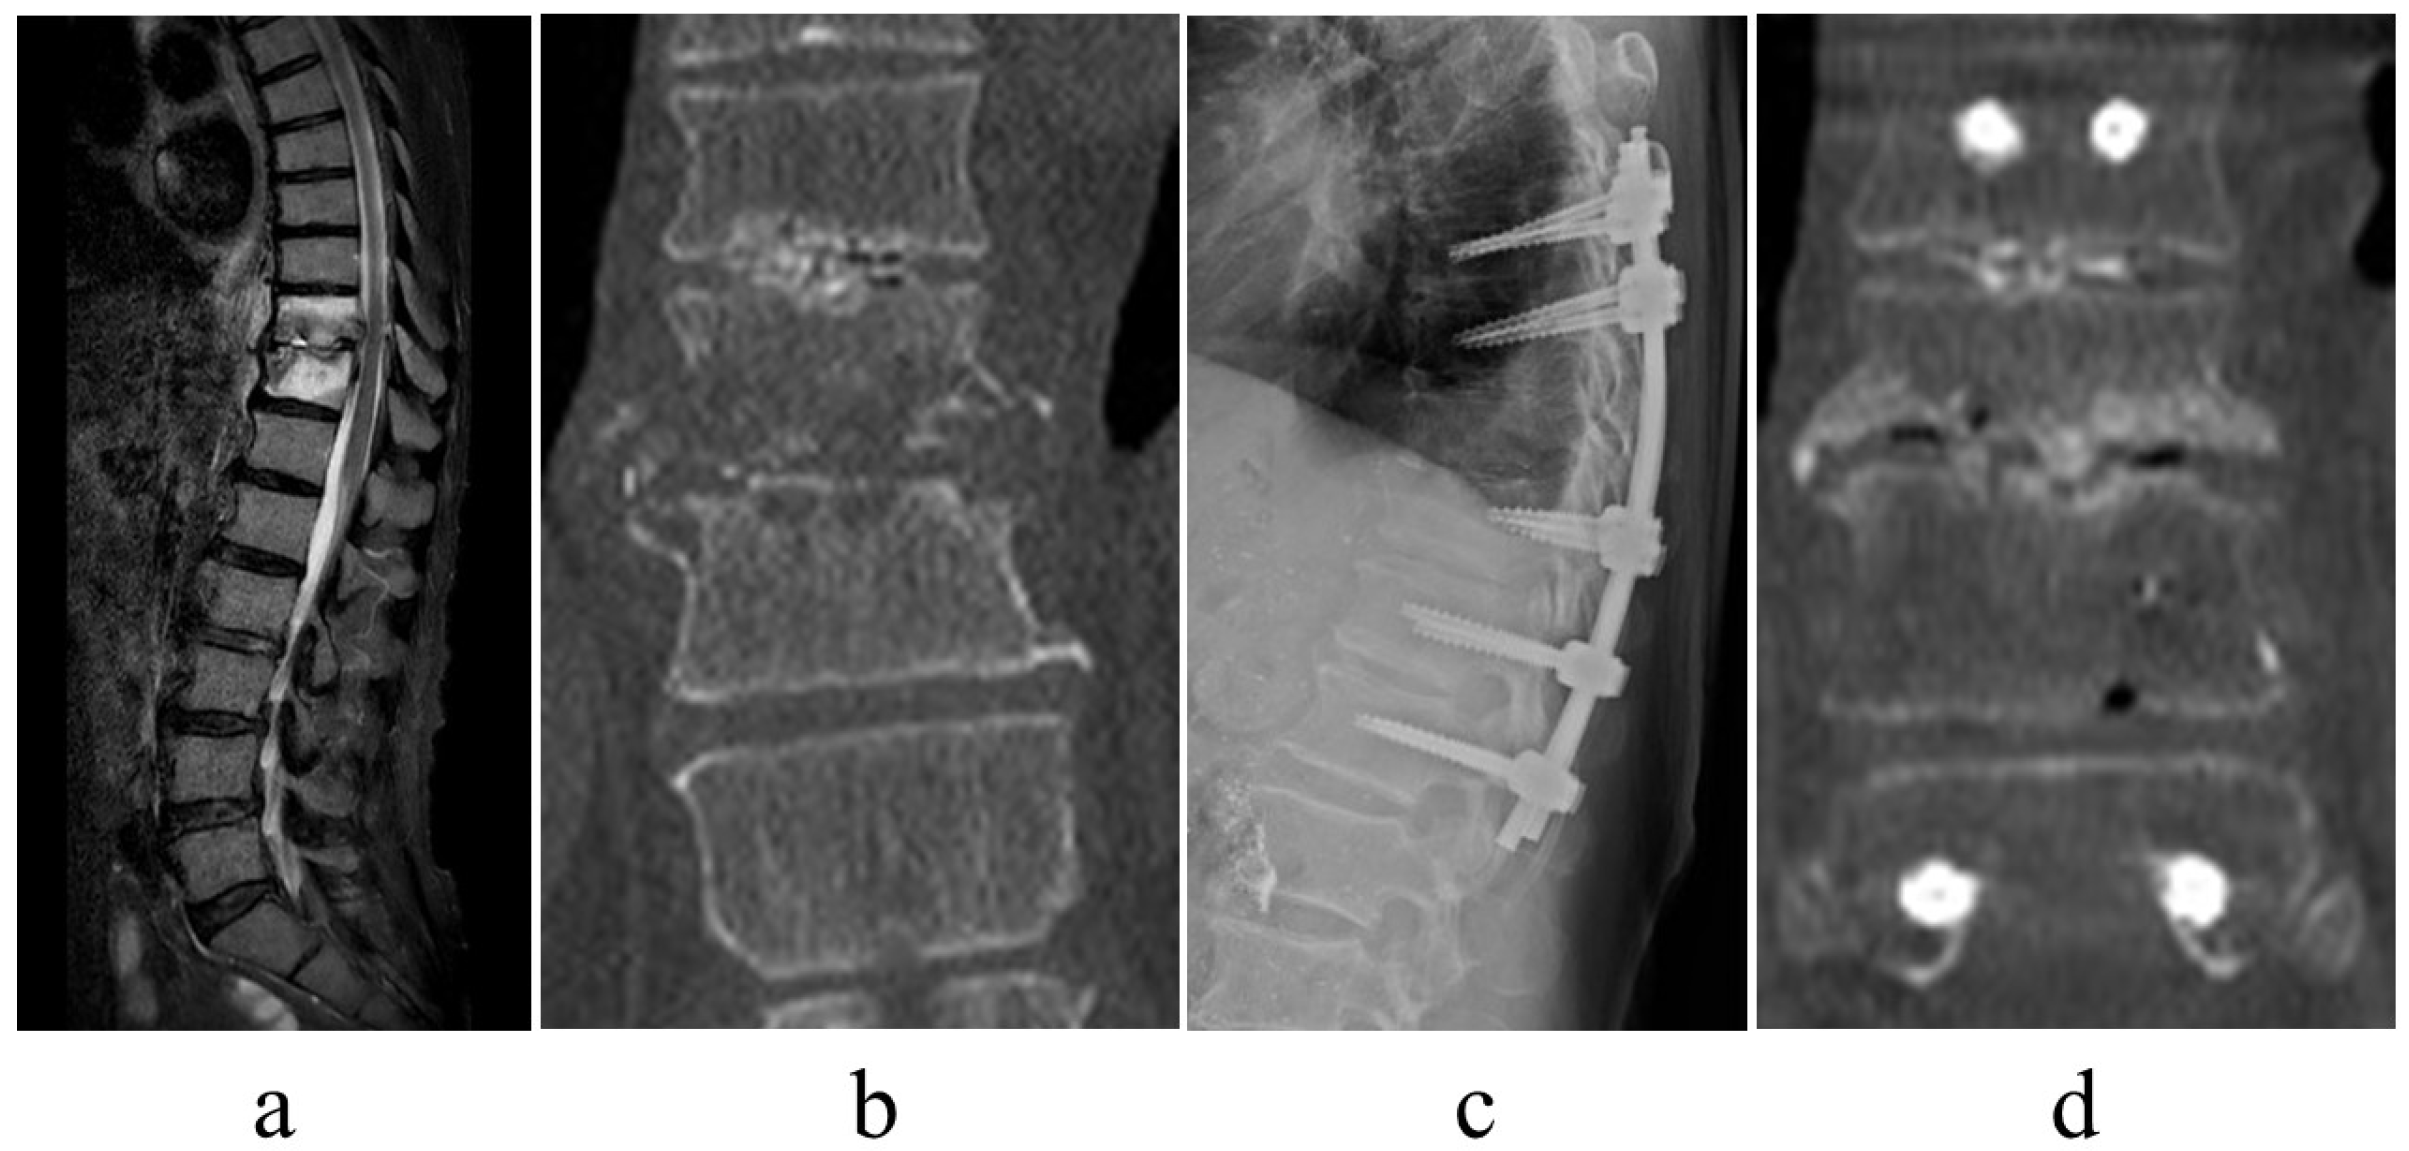

Treatment of Thoracolumbar Pyogenic Spondylitis with Minimally Invasive Posterior Fixation without Anterior Lesion Debridement or Bone Grafting: A Multicenter Case Study

- Infection control. With minimally invasive posterior fixation and sensitive antibiotics, the inflammatory response normalized at an average of 42.8 days postoperatively. Previous reports stated that the period of normalization of the C-reactive protein concentration ranged from <1 month to 3 months; however, it was 42.8 days in this series [5,16]. In numerous patients, infection control was achieved without requiring additional surgery, thus implying that this technique is useful for infection control.

- Early ambulation. Less invasive procedures and pain reduction aid early ambulation. Herein, surgery significantly reduced pain (NRS for preoperative lower back pain was 5.9, which improved to 3.6 at the postoperative period of ambulation) and induced early ambulation (patients were able to ambulate at an average of 2.7 days postoperatively). For pain relief and time to ambulation, the results were comparable with those of previous studies [17,18]. Even in older patients, the minimally invasive procedure may enable early ambulation.

- Alignment maintenance. Local kyphosis, which is exacerbated by the destruction of the disk or vertebral body due to infection, is a measure of alignment maintenance. Minimally invasive posterior fixation improved local kyphosis by 6.6 degrees, with a postoperative correction loss of 3.6 degrees, which is comparable with results reported in previous studies (range: 3.4–6.8 degrees) [11,15,16]. These findings suggest that the range of fixation and fixation strength in this series were sufficient to maintain local alignment.